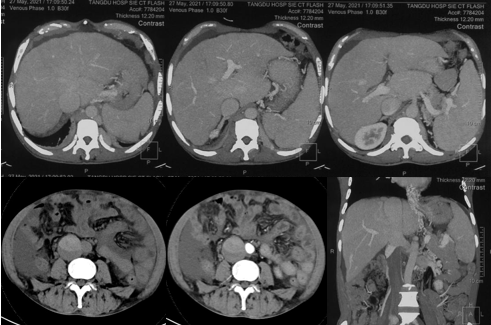

6月20日,患者及家屬懷揣著忐忑的心情來(lái)到西安國(guó)際醫(yī)學(xué)中心醫(yī)院找到韓國(guó)宏教授,韓教授詢(xún)問(wèn)病情后閱患者外院CT片,明確診斷布加綜合征,同時(shí)發(fā)現(xiàn)了一個(gè)新的問(wèn)題,在詢(xún)問(wèn)病史時(shí)了解到患者近一周雙下肢乏力伴腫脹明顯加重,遂立即安排了急診CT,證實(shí)下腔靜脈內(nèi)急性血栓形成!

6月22日,在韓國(guó)宏教授的帶領(lǐng)下,患者于消化介入診療中心行下腔靜脈開(kāi)通術(shù)。術(shù)中可見(jiàn):下腔靜脈全段擴(kuò)張,膜性閉塞,腎靜脈平面以下可見(jiàn)血栓形成并伴有粗大的側(cè)枝靜脈,遂對(duì)狹窄段球囊擴(kuò)張并植入支架,術(shù)后下腔靜脈血流通暢,側(cè)枝消失。術(shù)后第2天,患者腹壁靜脈曲張幾乎消失不見(jiàn),走路也輕快了許多。明明只是薄薄的一層膜,為什么開(kāi)通起來(lái)這么難?韓教授指出,盡管布加綜合征介入開(kāi)通技術(shù)已使創(chuàng)傷降到了最低,但受到患者個(gè)體差異及醫(yī)療水平參差不齊的限制,仍有可能出現(xiàn)嚴(yán)重的并發(fā)癥,主要包括:心包積血、縱隔血腫、心包填塞甚至下腔靜脈撕裂引起的大出血等。而其發(fā)生率與術(shù)者的操作熟練程度及經(jīng)驗(yàn)有很大的關(guān)系。